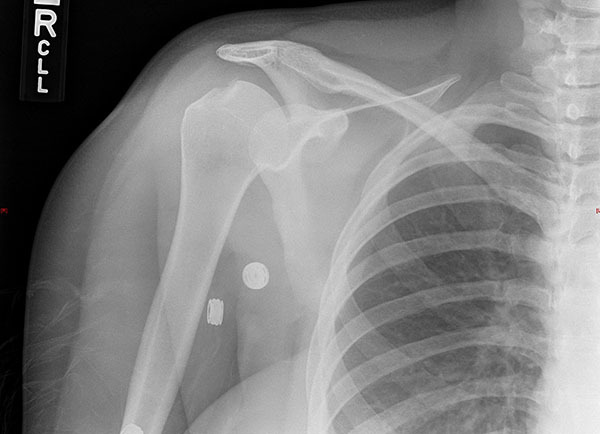

Complications of shoulder dislocations include shoulder instability, fractures, and neurovascular injuries. Anterior dislocations may be complicated by a Hill-Sachs lesion, which is an osseous defect on the humeral head. (See Figure 5.) The incidence reaches 100% with recurrent anterior shoulder dislocations and may be associated with glenoid bone loss. Treatment includes nonsurgical management focused on physical therapy and rehabilitation.48

Figure 5. Hill Sachs Deformity |

![]() |

Courtesy of J. Stephan Stapczynski, MD. |